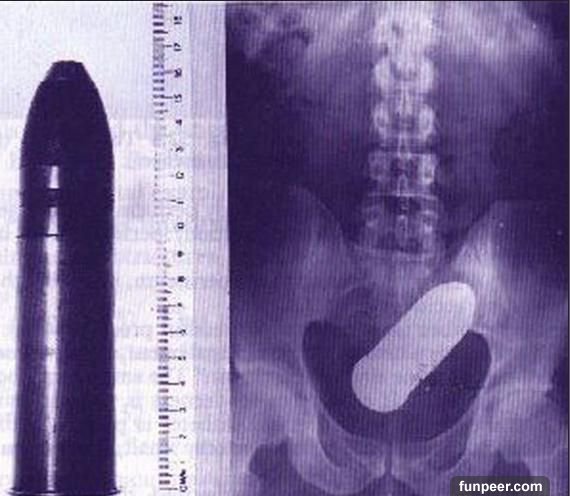

使用性用品也不一定安全

有些人以為,到性用品店買個性工具總不會有危險了吧?錯!使用性用品也可能會出意外的。看看上面這兩個X光片,可憐的使用者居然把震動棒和假陰莖“安家”在體內了。所以提醒各位有意使用性工具的網友:1.購買性工具一定不能貪便宜,要購買品質信得過的;2.使用時要嚴格遵照使用說明,千萬不能隨心所欲;3.正規廠家的產品也難免會有某些出現意外,所以使用前要嚴格檢查它是否安全。

【猜一猜】你能從這些X光片中看出他/她們使用的是什麼東西進行自慰嗎?